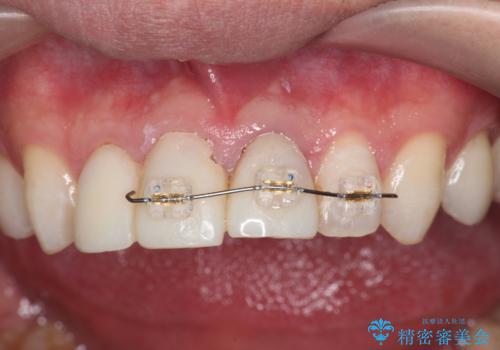

- 部分ワイヤー矯正

- 前歯の変色や形態を含む、見た目を改善したいと希望され来院されました。

視診・X線検査・歯周組織検査より下記のような問題が列挙され、長期的な予後を見込むために一つづつ問題の解決を計ります。

・不十分な根管治療 →マイクロスコープを用いる精密根管医療

・歯の変色 →ジルコニアクラウンの製作

・歯肉縁下カリエス →部分矯正による歯の挺出・歯周外科

歯の挺出を行ったことで歯ぐきの腫れも改善され、安定した歯周環境下でのセラミッククラウン治療を行うことができました。